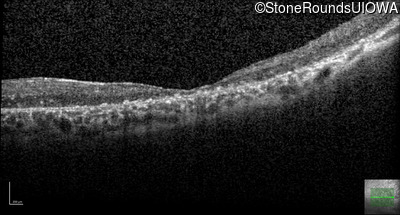

Age at visit: 41 years

This 41 year old man first came to medical attention at age 18 months when exotropia and amblyopia of his right eye were discovered. At age 11 vitreous strands and retinal vascular sheathing were seen. He has had poor night vision and constricted visual fields since his late teens. Later, at age 44 a traction retinal detachment was noted in his left eye and was treated with a scleral buckle.